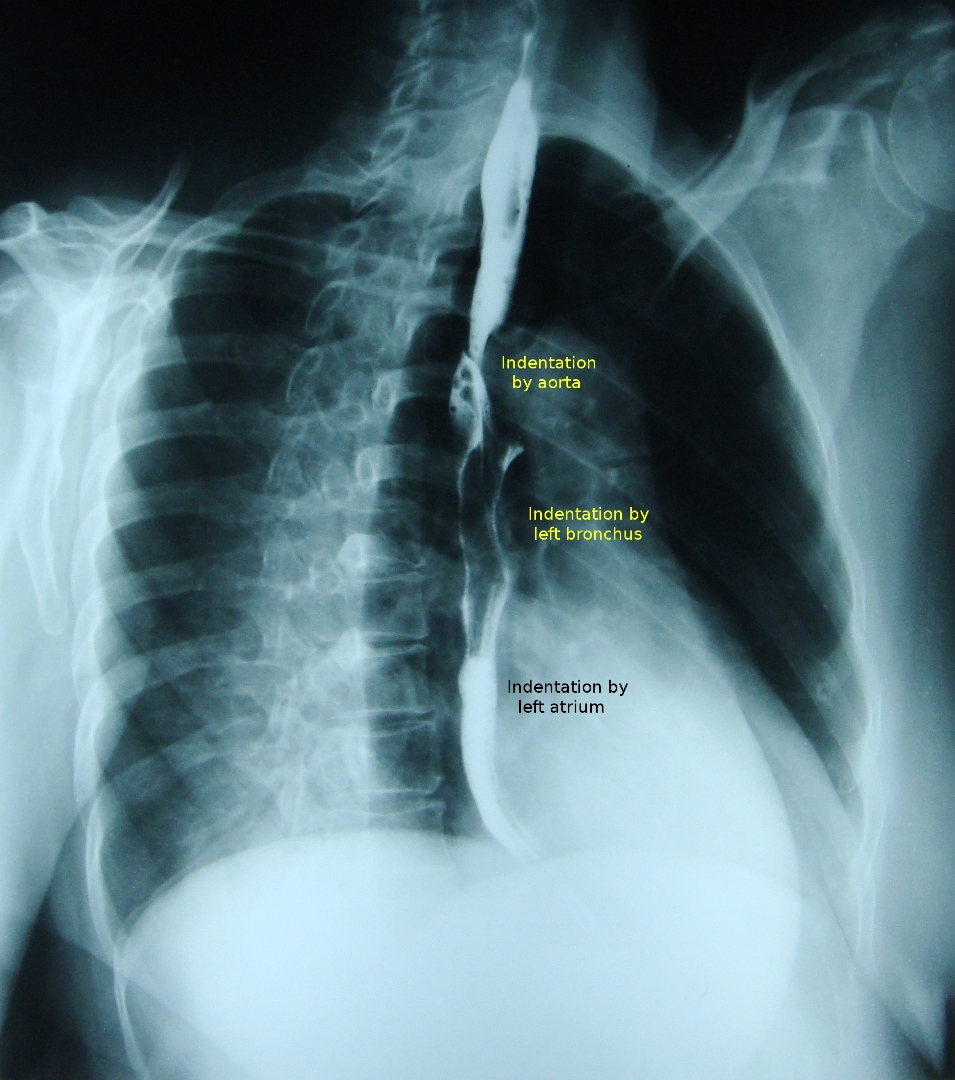

Normal indentations on the esophagus in barium swallow …

barium swallow esophagram, x-ray swallow goiter trachea repair, barium swallow test, barium swallow study, normal barium swallow, zenker’s diverticulum swallow symptoms, funny x-ray